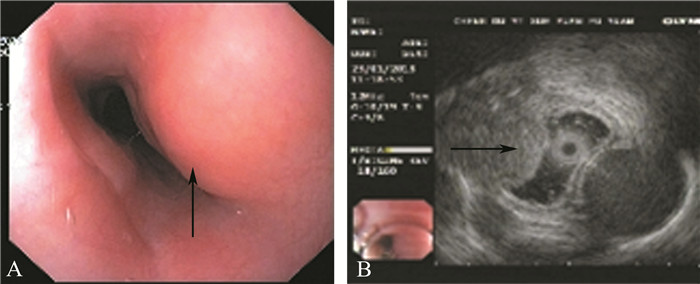

病例报告 一、病例资料患者女,20岁。因“吞咽困难1个月余”于2018年1月28日入院,既往无肺结核病史,家族中无结核感染病史。体格检查:体温36.5 ℃,心率98次/分,呼吸18次/分,血压112/86 mm Hg (1 mm Hg=0.133 kPa),双肺呼吸运动均匀对称,语音震颤未见明显增强或减弱,叩诊呈清音双肺未闻及明显湿啰音及胸膜摩擦音,腹部查体未见异常。辅助检查:普通胃镜检查提示距门齿25 cm处可见一大小约2.1 cm×2.3 cm的黏膜隆起,表面光滑;考虑为:黏膜下来源?外压?(图 1A)。经电子胃镜超声示黏膜肌层中低回声团块,表面黏膜完整,考虑黏膜下来源,平滑肌瘤可能(图 1B)。胸部CT平扫示纵隔内气管隆突下方软组织肿块影,大小约2.7 cm×2.8 cm,其内可见钙化影,与邻近食管分界欠清,性质?(图 2A)。胸部增强CT示气管隆突下方见一大小约为2.9 cm×2.6 cm的软组织肿块影,可见部分钙化影,边界不清,增强扫描呈轻度强化,考虑为:增大淋巴结?(图 2B)。上消化道钡剂造影示黏膜规则,管壁光滑柔软,未见异常病变。入院后行血液分析、肝肾功能均未见异常,痰涂片未见结核杆菌,ESR正常,结核抗体试验阴性。

图 1 食管结核患者胃镜及超声胃镜图 A:胃镜提示食管黏膜有规则的隆起病变(箭头);B:超声胃镜示食管黏膜肌层中低回声团块(箭头),考虑为平滑肌瘤可能 |